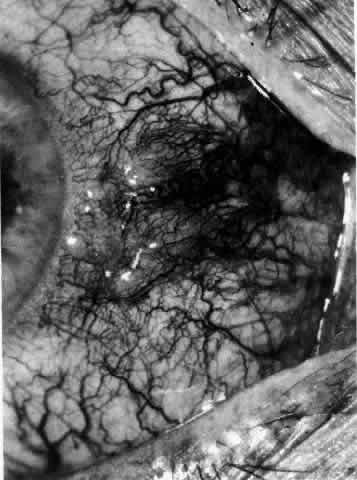

Necrotizing Anterior Scleritis with Inflammation

Patients with necrotizing anterior scleritis with inflammation not only suffer extremes of discomfort but are in serious danger of losing an eye. Therefore, it is of great importance that the condition be detected early and treated adequately. (It is of equal importance that those varieties of scleral inflammation that are not destructive to the eye should not be treated with drugs that are themselves dangerous.) Accurate diagnosis is the key.

Necrotizing scleritis accompanied by inflammation is always painful, waking the patient at night, increasing in intensity day by day, and leading to severe distress. The sclera is swollen, and the overlying inflammation is localized to the center of a lesion or to either end of an extending lesion (Fig. 37; Color Plate 1D). After inflammation, the sclera becomes transparent so that the underlying choroidal pigment becomes visible when viewed in daylight (Fig. 38). These areas may be invisible with the slit lamp. The area of inflammation extends outward around the globe from the original site of inflammation, often joining with other areas of scleritis that have subsequently appeared. If the inflammation is not suppressed, the process will progress around the globe until the whole anterior segment is involved (Fig. 39).

The characteristic features of necrotizing scleritis on fluorescein angiography are hypoperfusion and, eventually, nonperfusion of the vascular networks (Figs. 40 through 43).26 The initial changes are on the venous side of the capillary network; the transit time of the dye increases even if the eye is red and congested. If the disease process persists or has been present for a long time, thrombosis and permanent vaso-occlusive changes occur. These vessels (or the occluded capillary network) are bypassed by the opening of anastomotic channels. New vessels in a granuloma give rise to deep intrascleral leakage of dye (see Fig. 43). Conjunctival and episcleral involvement by the destructive change is late but is always preceded by vaso-occlusive changes that can sometimes be detected with use of the red-free light on the slit lamp (Figs. 44 and 45).

Fig. 40. Early necrotizing scleritis. There is characteristic yellow discoloration of the sclera underlying the conjunctiva at a point of necrosis. In this instance a small filament of tissue has penetrated the conjunctiva.

Fig. 41. Late stage of fluorescein angiogram adjacent to the site of necrosis in the same patient as in Figure 40. Although the eye is uniformly congested, the area near the necrosis shows vascular shutdown, whereas the rest of the conjunctiva and episclera is normally perfused.

Fig. 42. Late arterial phase of fluorescein angiogram in a patient with necrotizing scleritis. All the vessels except the main trunk and the vessels around the limbal perforating vessels are occluded and remain unperfused throughout the angiogram.

Fig. 43. Late venous phase of angiogram of a patient with necrotizing scleritis showing late deep leakage from vessels on the surface of the sclera and leakage of the capillary network at the limbus and the vessels draining it, together with poor or absent perfusion of the remaining vessels.

Fig. 44. Necrotizing scleritis. An avascular patch is seen in red-free light. If left untreated, this will progress to the situation found in Figure 45.

Fig. 45. Necrotizing scleritis. An area of necrosis is evident in the eye of this patient with localized Wegener's granulomatosis. The conjunctiva adjacent to the white necrotic tissue becomes adherent to the underlying episclera.